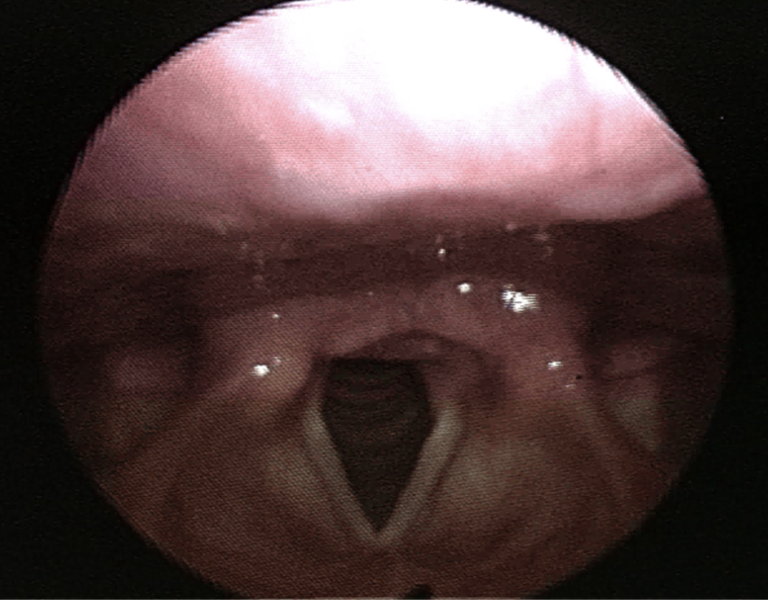

bronchoscopy of normal larynx

pretty nice and pink, can visualize vocal cords

nice little triangle